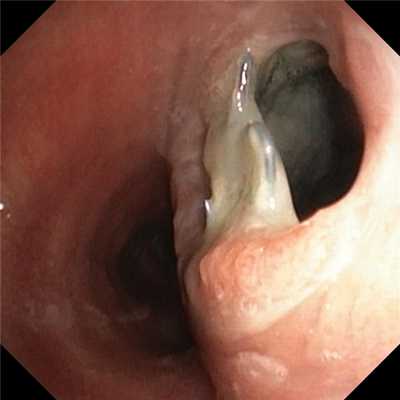

Состояние после вклинения камня и образования супрапапиллярного свища